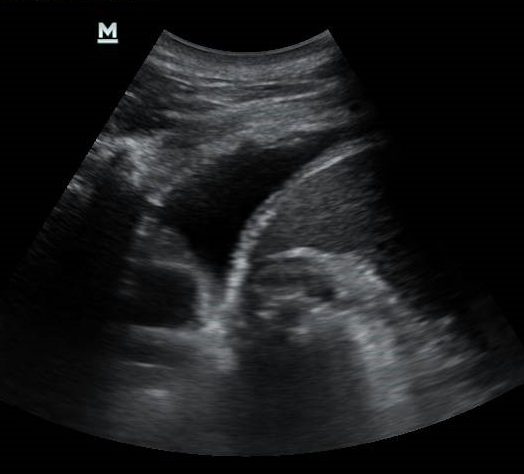

Sepertimana yang kita sedia maklum, pesakit yang dijangkiti Covid-19, dibahagikan kepada beberapa katogeri yakni katogeri 1 hingga 5. Mereka yang diklasifikasikan sebagai katogeri 4b atau 5 lazimnya memerlukan bantuan pernafasan iaitu intubasi(ditidurkan dalam istilah umum). Sekiranya kandungan kehamilan telah besar yakni 26 minggu keatas, ia secara tidak langsung ia akan menyengkang pergerakan diafram di dada. Ini boleh membantut pertukaran oksigen di dalam badan disebabkan kapasiti paru-paru menjadi kecil. Bagi membolehkan paru-paru kembali berkembang secara maksimum, bayi yang dikandung haruslah dikeluarkan dari rahim ibu. Sekiranya bayi yang dilahirkan sebelum 36 minggu kehamilan, ia dianggap sebagai kelahiran pramatang. Mereka yang didiagnos sebagai katogeri 1-3 lazimnya tidak memerlukan kepada intubasi. Oleh itu mereka tidak perlu kepada kelahiran pramatang.

4. Bolehkah virus itu disebar dari ibu ke bayi dalam kandungan, atau semasa kelahiran?

Terdapat beberapa laporan menyatakan kemungkinan transmisi virus dari ibu kepada bayi dalam kandungan boleh berlaku sewaktu kehamilan. Ini dibuktikan dengan penemuaan virus pada uri(placenta), tali pusat bayi, air ketumban serta bayi yang diasingkan selepas kelahiran didapati positif dengan jangkitan Covid-19. Namun peratusannya sangat kecil yakni kurang dari 3%. Lazimnya, bayi ini akan diuji untuk jangkitan virus pada hari pertama kelahirannya. Sekiranya keputusan adalah negatif, pemeriksaan ulangan akan dibuat pada hari ketiga kelahiran. Kebanyakan bayi mempunyai result yang negatif pada hari pertama serta hari ketiga kehamilan.

Namun sekiranya pembedahan ini terpaksa dilakukan pada wanita hamil katogeri 4 atau 5 yang mana kandungan masih belum matang, sudah tentu akan ada komplikasi kepada  bayi tersebut. Ini kerana bayi tersebut terdedah kepada risiko berkaitan dengan pramatang yang mungkin memudaratkan di masa akan datang. Keputusan untuk mengeluarkan bayi pramatang haruslah dbincang bersama pakar kanak-kanak serta pakar bius.  Alat pernafasan bayi(ventilator) haruslah disediakan bagi menyambut bayi pramatang ini. Keputusan untuk mengeluarkan bayi ini adalah penting sebagai usaha untuk merawat paru-paru ibu yang telah terkesan dengan penyakit Covid-19.

Apabila seseorang itu berada dalam posisi melentang, jantung serta organ dalaman seperti usus, hati dan limpa akan menekan paru-paru. Ini membatas perkembangan paru-paru tersebut serta pergerakan diafram. Kehadiran bayi didalam rahim yang besar juga akan memburukkan lagi keadaan ini. Pada masa yang sama disebabkan graviti, terdapat perbezaan di antara tekanan di antara paru-paru di bahagian atas dan bawah yang menyebabkan alveoli di bahagian bawah menguncup. Kadar aliran darah adalah tinggi dibahagian bawah namun pertukaran oksigen tidak berlaku kerana alveoli telah menguncup. Apabila pesakit ditelangkupkan, pertukaran posisi ini membantu pengembangan alveoli yang menguncup tadi. Alveoli ini boleh berkembang dengan baik dan ini membantu dalam pertukaran oksigen-karbon dioksida di dalam badan. Apabila ini berlaku, paras oksigen dapat dipulihkan.

Kehadiran bayi dalam rahim menyukarkan pertukaran posisi ini. Setelah diambil kira risiko kepada ibu, kelahiran secara pembedahan caesarean harus dilakukan dalam usaha untuk membantu meningkatkan kadar oksigen di dalam badan wanita tersebut.